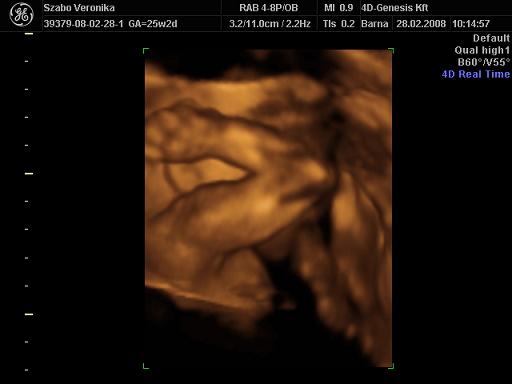

És egy tappancs 2008.03.08 19:45